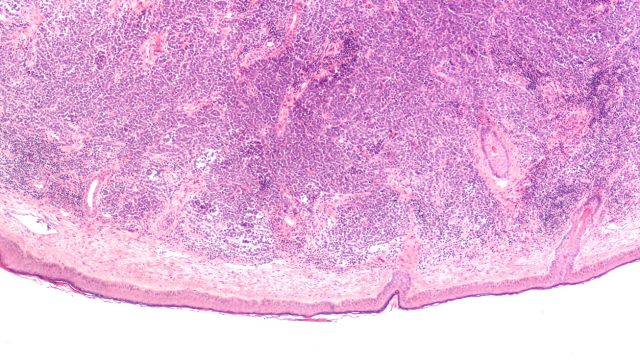

For example, some studies have indicated they reduce the risk of diabetic retinopathy, the leading cause of blindness among working-age adults. More than 90% of people with type 1 diabetes and 50-60% of those with type 2 diabetes develop this condition, in which high blood sugar levels damage blood vessels in the light-sensitive tissue at the back of the eye.

For the lab-based study, human retinal endothelial cells were treated with a range of different concentrations of semaglutide. The cells were kept in media with high glucose levels and oxidative stress (in which there are more free radicals than antioxidants) for 24 hours.